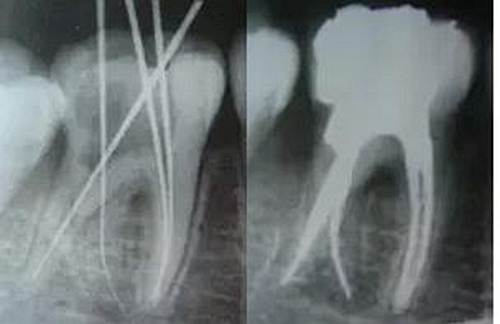

最后來玩一個根管治療質(zhì)量的評估——下圖是武大彭彬教授的一個病例,仔細(xì)觀察可以挑出一點問題,但問題事出有因!看看你的“眼力”如何——問題在那里?教授的專業(yè)水平是不用懷疑的,那么事出的原因可能是什么?

問題答案:這個病例的問題主要反應(yīng)在開髓的洞形修整,注意觀察該牙X-RAY的左側(cè)洞壁,如果常規(guī)情況制備成這樣是由于裂鉆破壞了洞壁和洞底所形成的臺階。如果評估根管治療的質(zhì)量那是要扣分的!但這個病例仔細(xì)觀察洞壁形態(tài)就可以看出:該病例屬于再治療的病例,因此還是屬于一個理想的病例。